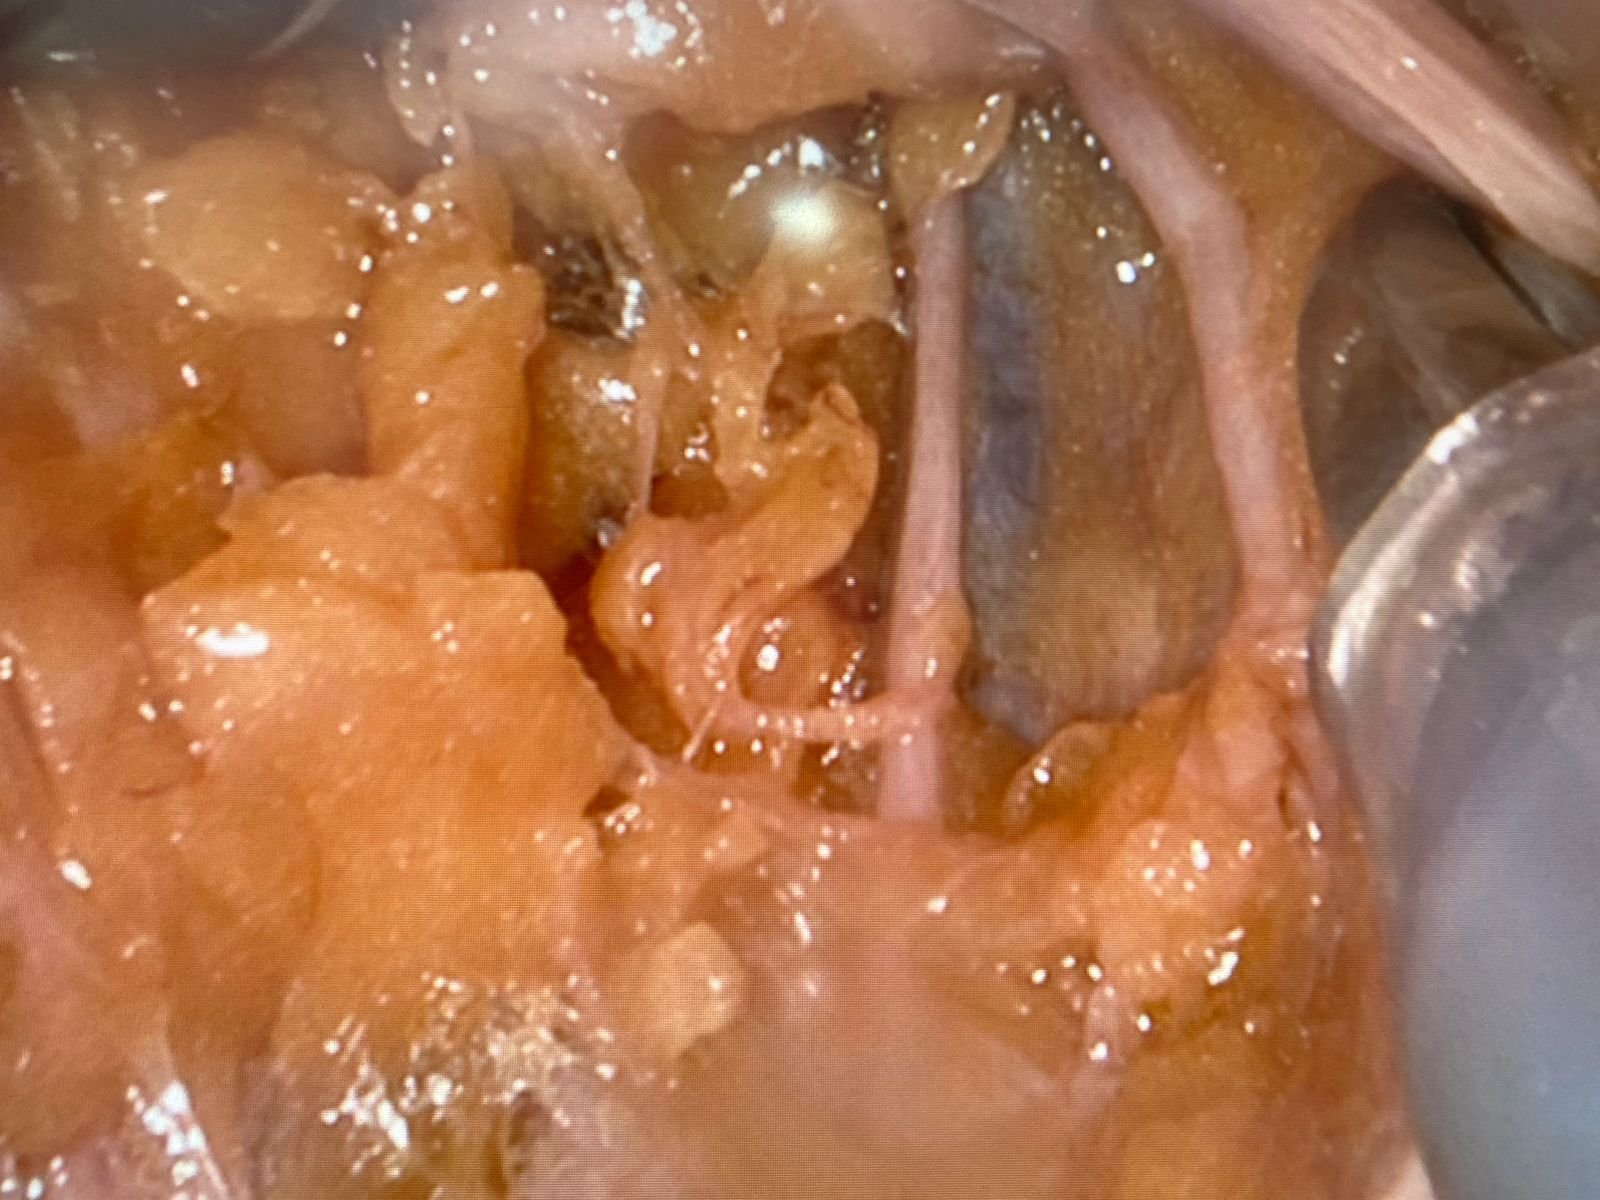

Upskilling of surgical techniques and ones skills is a very important part in the career of any surgeon.. In today’s world cadaveric dissection is one of the most useful way of acquiring new surgical skill set and refinement of the already acquired ones.Happy to be as a part of the Advanced hands on Robotic Gynec cadaveric training program as an expert faculty in association with Intuitive surgicals at the MS Ramiah cadaveric lab.Best wishes to the Gyn surgeons who attended.Greatful to the people and the family who donate the bodies for Rescearch and educational purposes!